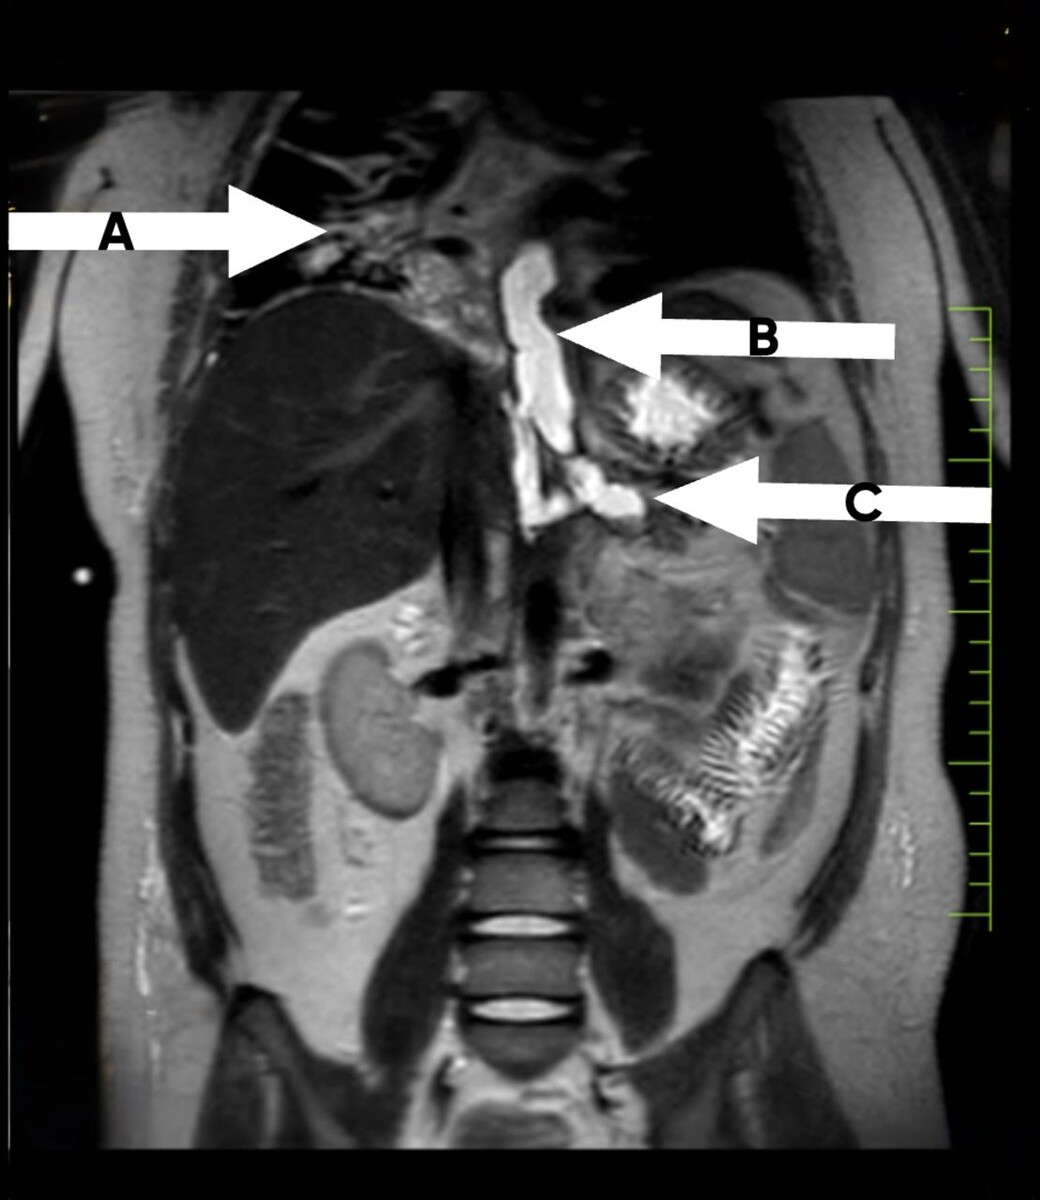

Магнитно-резонансная томография выявила панкреатит с образованием трубчатых кист в дистальных отделах тела и хвоста поджелудочной железы, распространяющихся сзади в забрюшинном пространстве и затем проходящих сверху через пищеводный проход диафрагмы в правую плевральную полость. Также было обнаружено узкое сообщение с левой плевральной полостью.